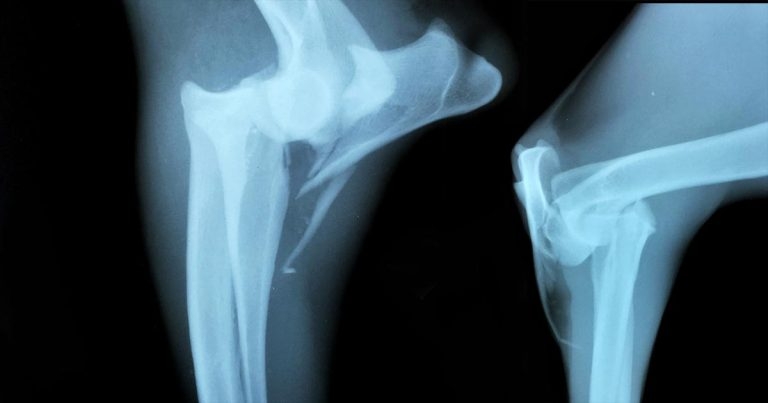

Figure 1. Lateral (left) and craniocaudal views of the right elbow.

In clear discomfort, swelling and bruising is noted around the elbow, with asynchronous movement in the distal limb. On clinical examination, crepitus associated with manipulation of the elbow is noted. Radiographs of the elbow are presented in Figure 1.

The radiographs show comminution of the proximal part of the ulna, extending to the olecranon. Due to the pull of the triceps, the proximal ulnar fragment and anconeal process have been displaced proximally.

Concomitant cranial luxation of the radial head is present. The nature of the injury suggests damage to the medial collateral ligament has also occurred.